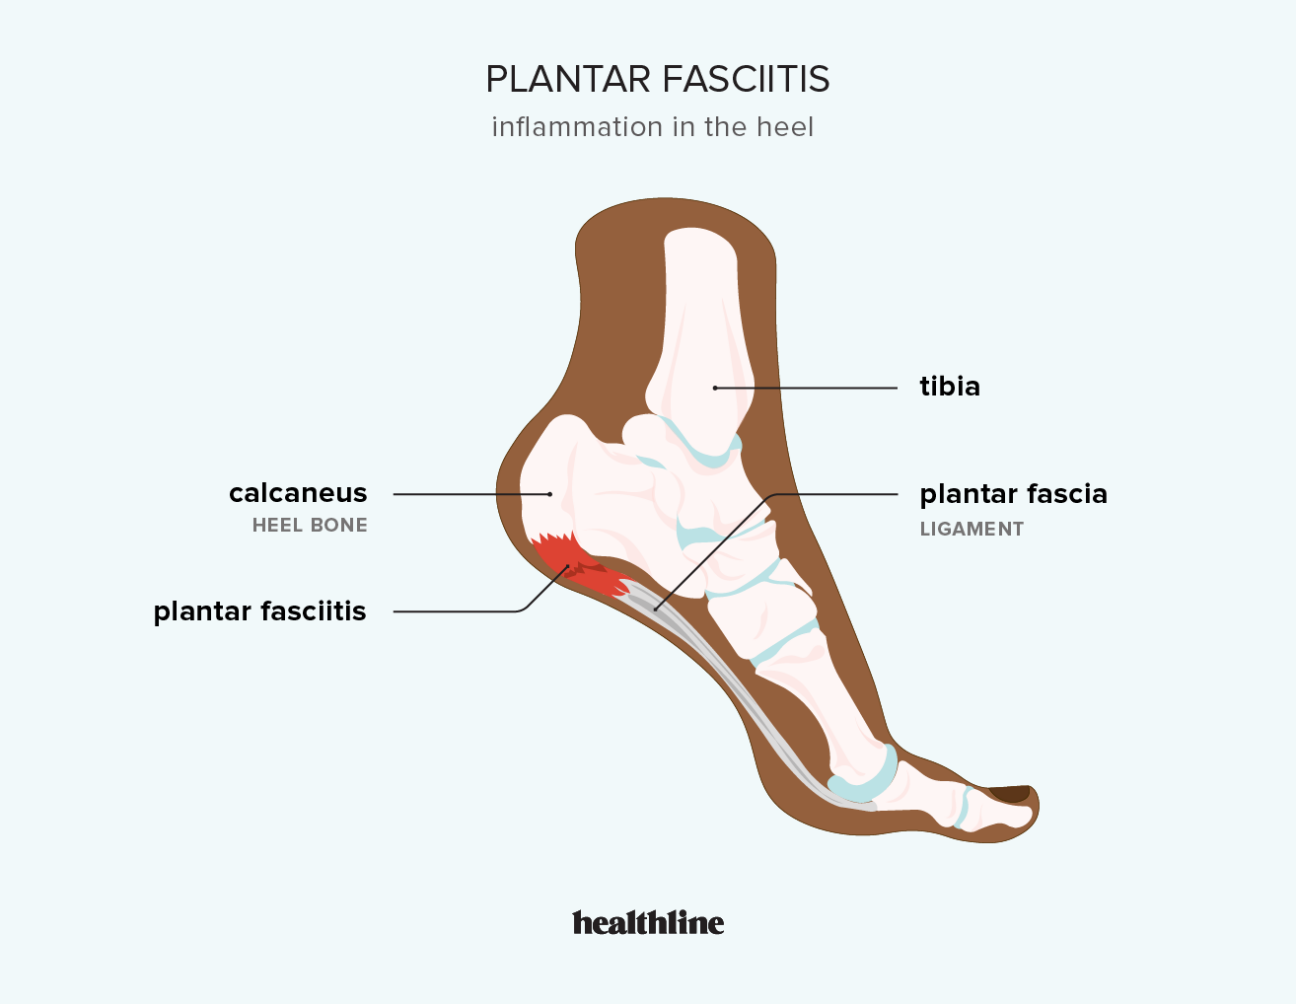

Can Plantar Fasciitis Cause Calf Pain Sidekick Blog new arrivals, My calves and feet hurt do I have plantar fasciitis Kelly new arrivals, Are You Sure It s Plantar Fasciitis Think Again. Rehab Renegade new arrivals, Trigger Points and Plantar Fasciitis Body Heal Therapy new arrivals, Relief plantar fasciitis pain in calf by stretching and proper support new arrivals, Plantar Fasciitis Treatment Oakville Shockwave Therapy new arrivals, Plantar Fasciitis Symptoms Causes Treatment Options new arrivals, Part One Stretching For Plantar Fasciitis new arrivals, Plantar fasciitis treatment symptoms and causes healthdirect new arrivals, Plantar Fasciitis Treatment Calf Stretches new arrivals, ProStretch The Original Calf Stretcher and Foot Rocker for Plantar new arrivals, Treating Plantar Fasciitis with RockTape RockPods RockTape new arrivals, Plantar fasciitis can be a very NeuroKinetic Therapy Facebook new arrivals, plantar fasciitis new arrivals, Plantar Fasciitis Exercises to Cure Heel Pain sFera Fitness new arrivals, Are You Sure It s Plantar Fasciitis Think Again. Rehab Renegade new arrivals, Tight Calves and Plantar Fasciitis Understanding the Link new arrivals, Calf Stretches For Plantar Fasciitis Achilles Tendonitis Right new arrivals, Calf.Bar Treat heel pain at the source Calf.bar Facebook new arrivals, Plantar Fasciitis Causes Symptoms Treatments and More new arrivals, Feet First Newry Foot Clinic Tight Calf muscles new arrivals, Plantar Fasciitis Arvada Sport Spine new arrivals, Stretches for Plantar Fasciitis You Need to Know for Pain Relief new arrivals, My calves and feet hurt do I have plantar fasciitis Kelly new arrivals, Plantar fasciitis Wikipedia new arrivals, Pain In The Back Of The Heel May Mean You Have Other Problems new arrivals, ProStretch Plus Customizable and Adjustable Calf Stretcher and Foot Rocker for Plantar Fasciitis Achilles Tendonitis and Tight Calves Made in USA new arrivals, Treating Plantar Fasciitis With Calf Stretches james new arrivals, How to treat plantar fasciitis new arrivals, 3 of the Most Common Risk Factors for Plantar Fasciitis John A new arrivals, 5 Ways To Treat Plantar Fasciitis Pain Road Runner Sports Road new arrivals, Plantar Fasciitis 10 Tools for Successful Patient Pain Relief new arrivals, This Stretch Helps Relieve Plantar Fasciitis and Heel Pain Live new arrivals, What s a Plantar Fasciitis EVA Orthotic Insoles Manufacturer new arrivals, Plantar fasciitis stretches 6 exercises for heel pain relief new arrivals, How to Heal Heel Pain from Plantar Fasciitis Foot Dynamics new arrivals, Best Calf Stretches For Plantar Fasciitis new arrivals, Treatments for Heel Pain Ottawa Foot Clinic new arrivals, Plantar Fasciitis ChiroKinetix Sports Medicine Clinic new arrivals, Trigger Points and Plantar Fasciitis Body Heal Therapy new arrivals, Acupuncture for Calf Trigger Points Morningside Acupuncture NYC new arrivals, Plantar Fasciitis Therapy Superior Physical Therapy new arrivals, Exercises to help prevent plantar fasciitis Mayo Clinic new arrivals, 5 Steps to Decreasing the Pain and Discomfort of Plantar Fasciitis new arrivals, Plantar Fasciitis What Is It Symptoms Treatment and More Osmosis new arrivals, Plantar Fasciitis Exercises new arrivals, Treating heel pain and plantar fasciitis at home Performance new arrivals, Plantar Fasciitis and Bone Spurs OrthoInfo AAOS new arrivals, Evaluation of Plantar Fasciitis Treatments Sydney Heel Pain Clinic new arrivals, Pin on My Style new arrivals.

Plantar fasciitis calf pain new arrivals